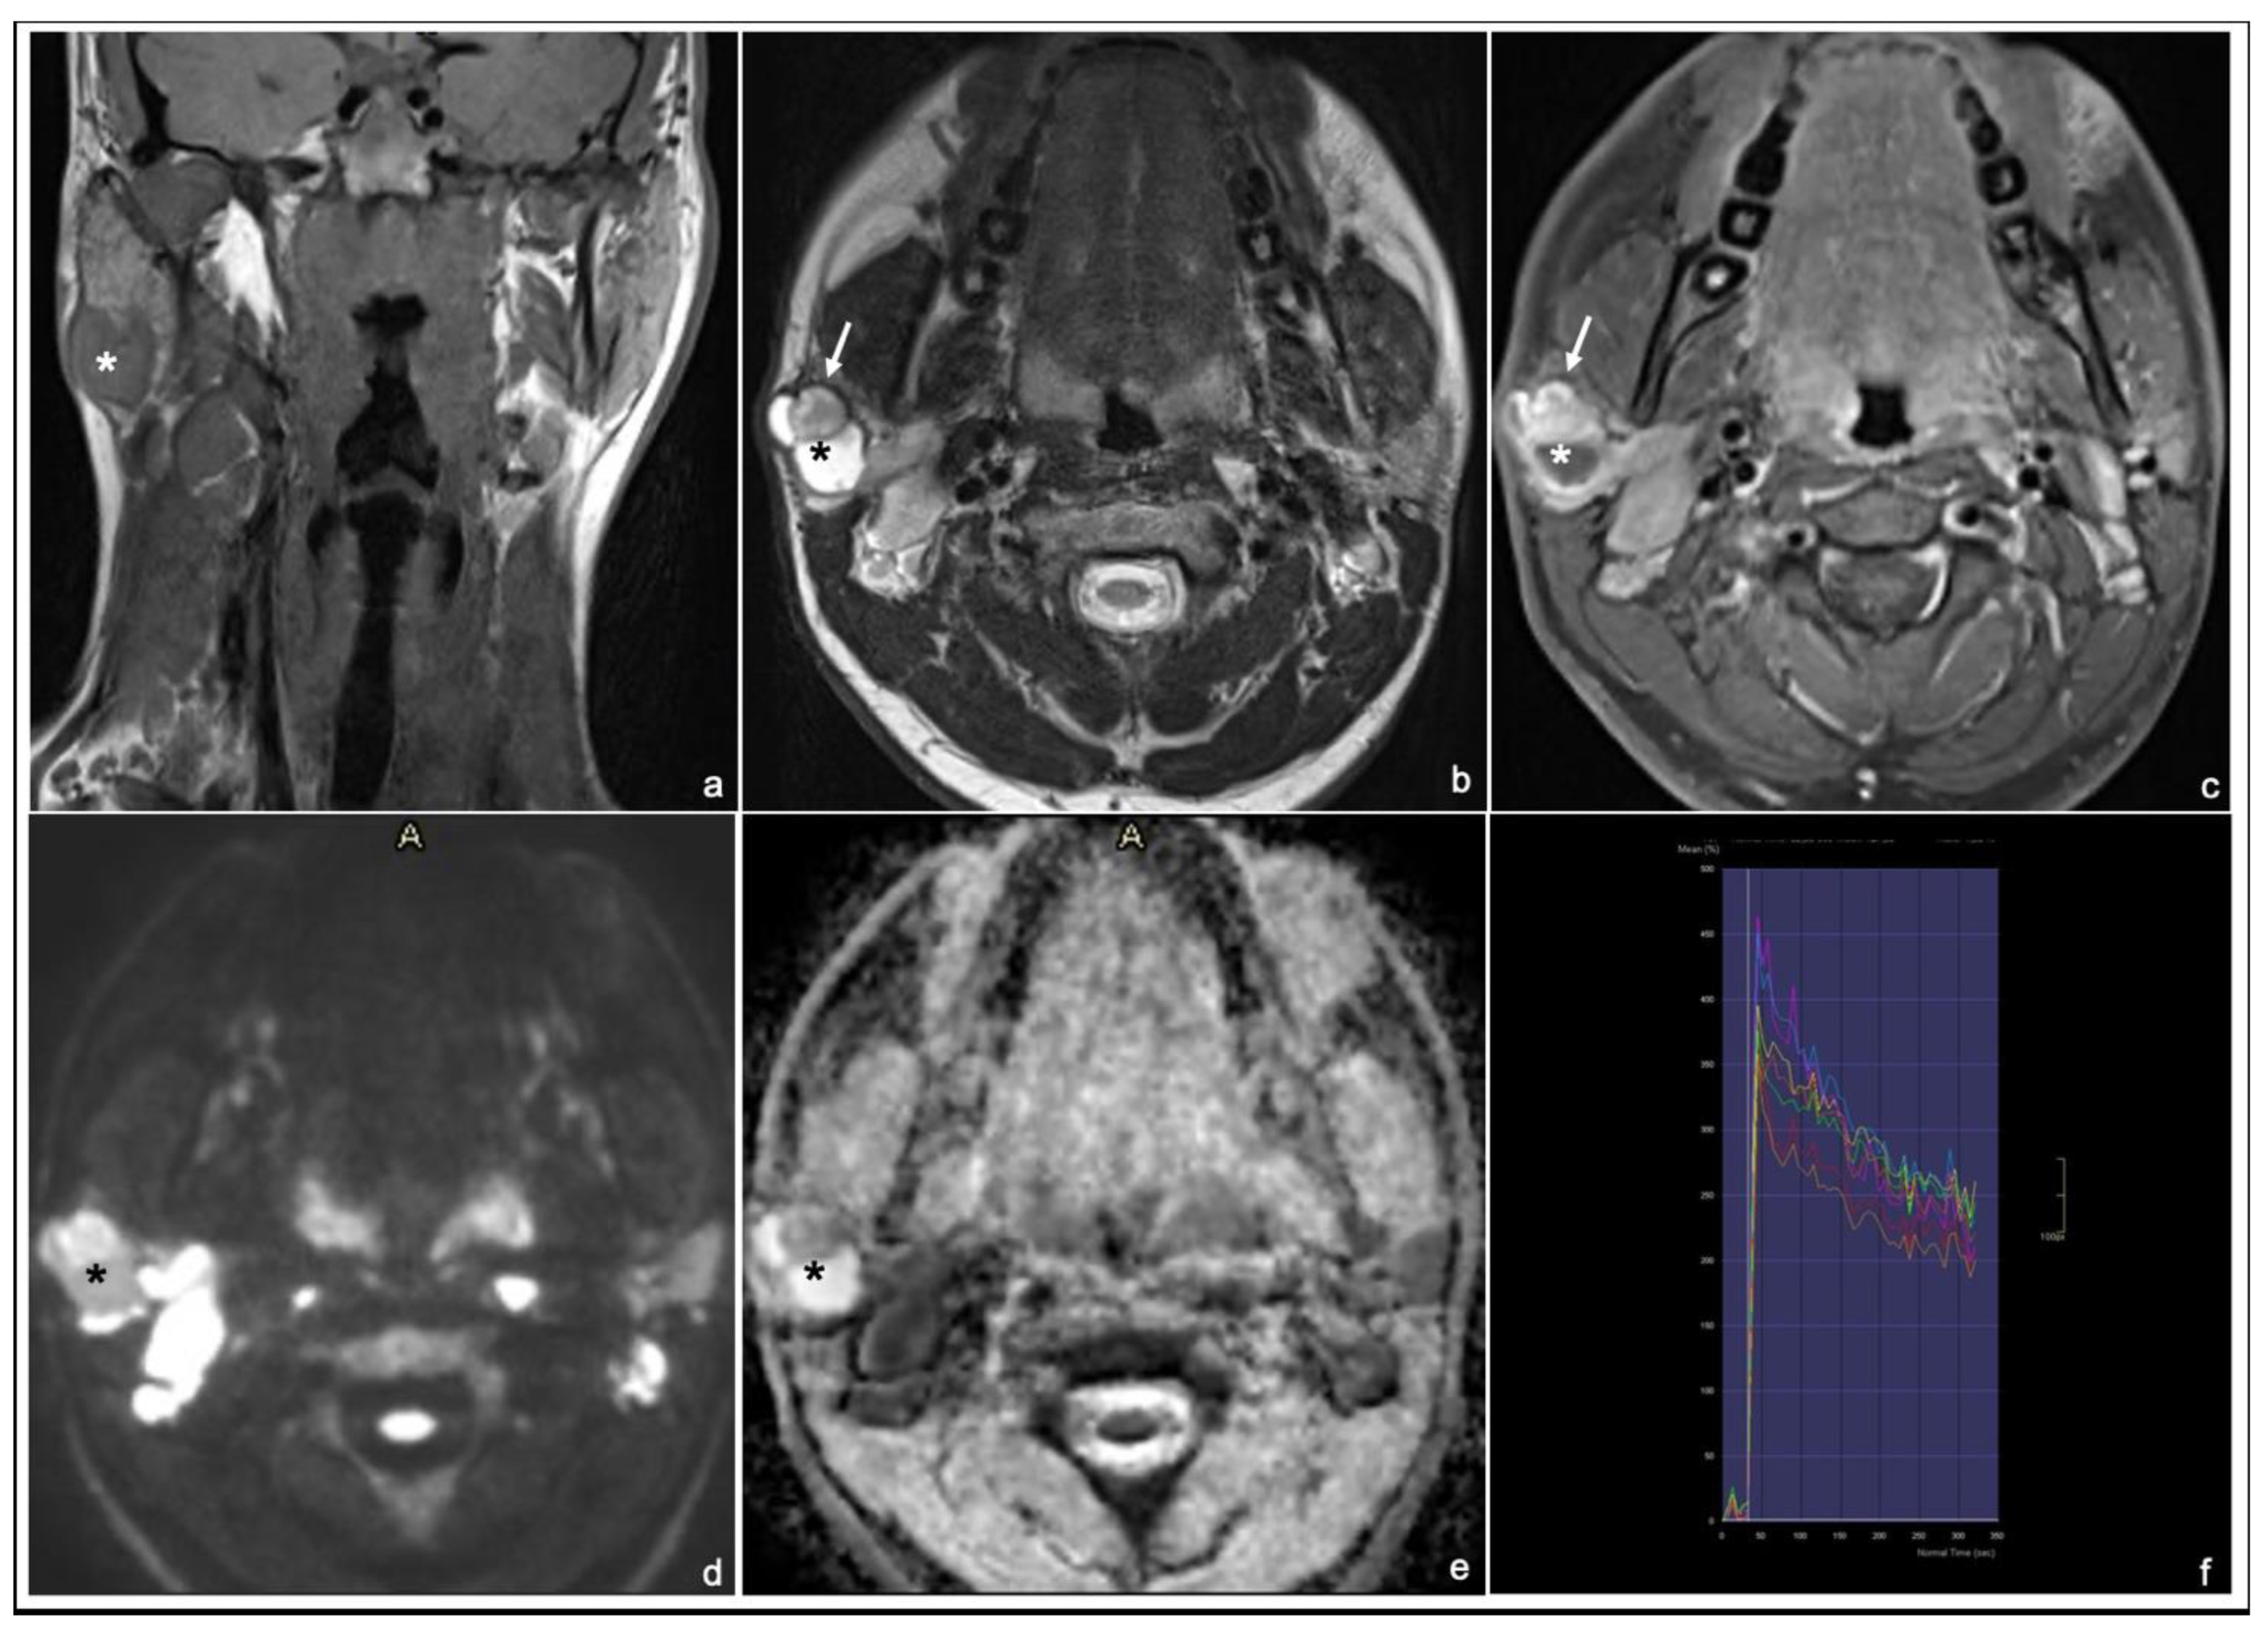

Typical MRI appearances of a pleomorphic adenoma, a Warthin tumor and a malignant tumor are shown in Figure 1, Figure 2 and Figure 3.

Figure 1. 54 years old man with a pleomorphic adenoma of the left parotid gland: coronal T1 TSE (a), axial T2 TSE (b), late T1 TSE FS + Gd (c), DWI and ADC map (d,e) and DCE signal intensity-time S(t)-curve type A (f). * tumor. The lesion has an inhomogeneous, intense enhancement after contrast agent injection (normalized late T1 + Gd SI ≥ 2) (c) and a high signal on T2 (normalized T2 SI ≥ 3.5) (b).